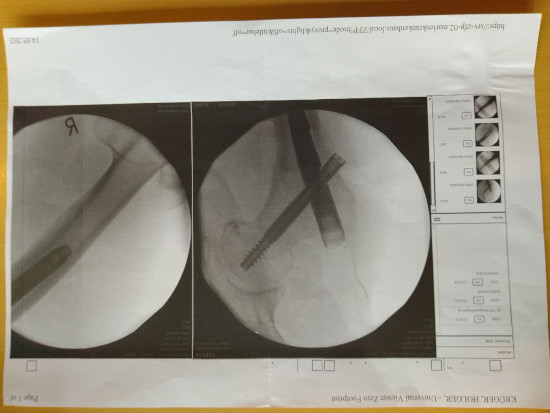

VERMUTUNG: Kunstfehler bei nichtnerücksichtigen von Allergien.!

… es ist bestimmt so dass eine Allergie erst bekannt wird wenn ein Arzt hier vielleicht Hautarzt eine Allergie durch einen Test einwandfrei diagnostiziert hat und diese Allergie auch beleghaft attestiert im Original oder amtlich beglaubigter Kopie der Operateur vor dem Zeitpunkt der OP vorliegt.! …

Wie verhält sich der Operateur wenn dieses Gutachten fehlt oder ein gegenteilige Urteil eines anderen Dermatologen zum Zeitpunkt der OP vorliegt und wegen dem Hohen Zeitdruck die Zeit für einen Vergleichtest oder Ereignistest feht.!???

Fall Sturz aus der Höhe und Fraktur der rechten Hüfte – Folgesymtomatik.! – 5 Monate später

- Schmerzen in beiden Beinen, besonders im rechten Knie bis zum fast follständigen Verlust der Gehfähigkeit bei starker Belastung

- ständiges Jucken am ganzen Körper besonders in einer warmen Umbebung

Vermutung: Mediziner brachten absichtlich mit den 2 Schrauben oder mit Medikamenten Materialien in meinen Körper auf die ich mit Jucken, Entzündung und Schmerzen stark allergisch reagiere.!??